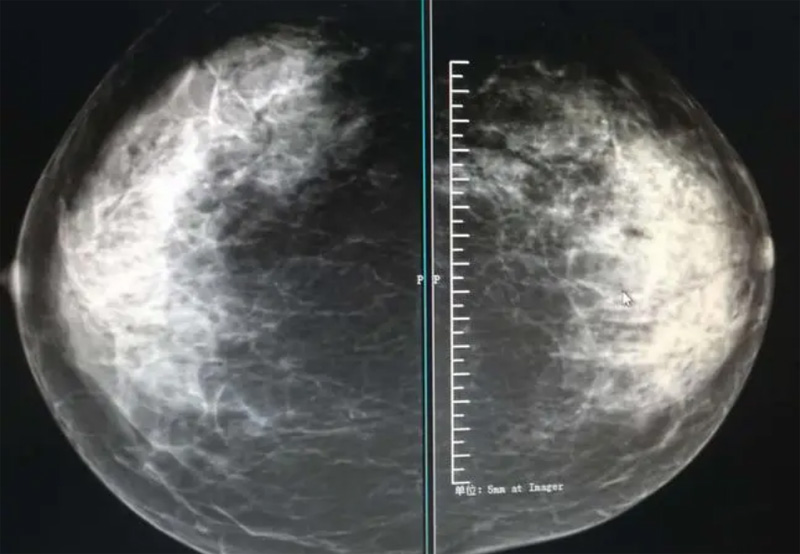

乳腺DR攝影體位有頭尾位及內外側斜位,

乳房在片子的中央,乳頭切線位,可見小部分胸大肌,內側乳腺組織應全部包括在片中,外側乳腺組織盡可能包括在片中。一張好的MLO位圖像顯示如下:乳房被推向前上,乳腺實質充分展開,胸大肌可見,較松弛,下緣達到乳頭水平,乳頭在切線位,部分腹壁包括在片中,但與下部乳腺分開,絕大部分乳腺實質顯示在片中。乳腺組織外緣可見乳頭的輪廓;乳腺后方的脂肪組織被很好地顯示出來,乳房無皺褶。對于CC位及MLO位顯示不良或未包全的乳腺實質,可以根據病灶位置的不同選擇以下體位:外內側位(LM)、內外側位(ML)、內側頭尾軸位(MCC)、外側頭尾軸位(LCC),尾葉位(CLEO)及乳溝位。在臨床實踐中,對于常規(guī)體位上發(fā)現的異常改變,可以進一步采取一些特殊的攝影技術,包括局部加壓攝影、放大攝影或局部加壓放大攝影技術。